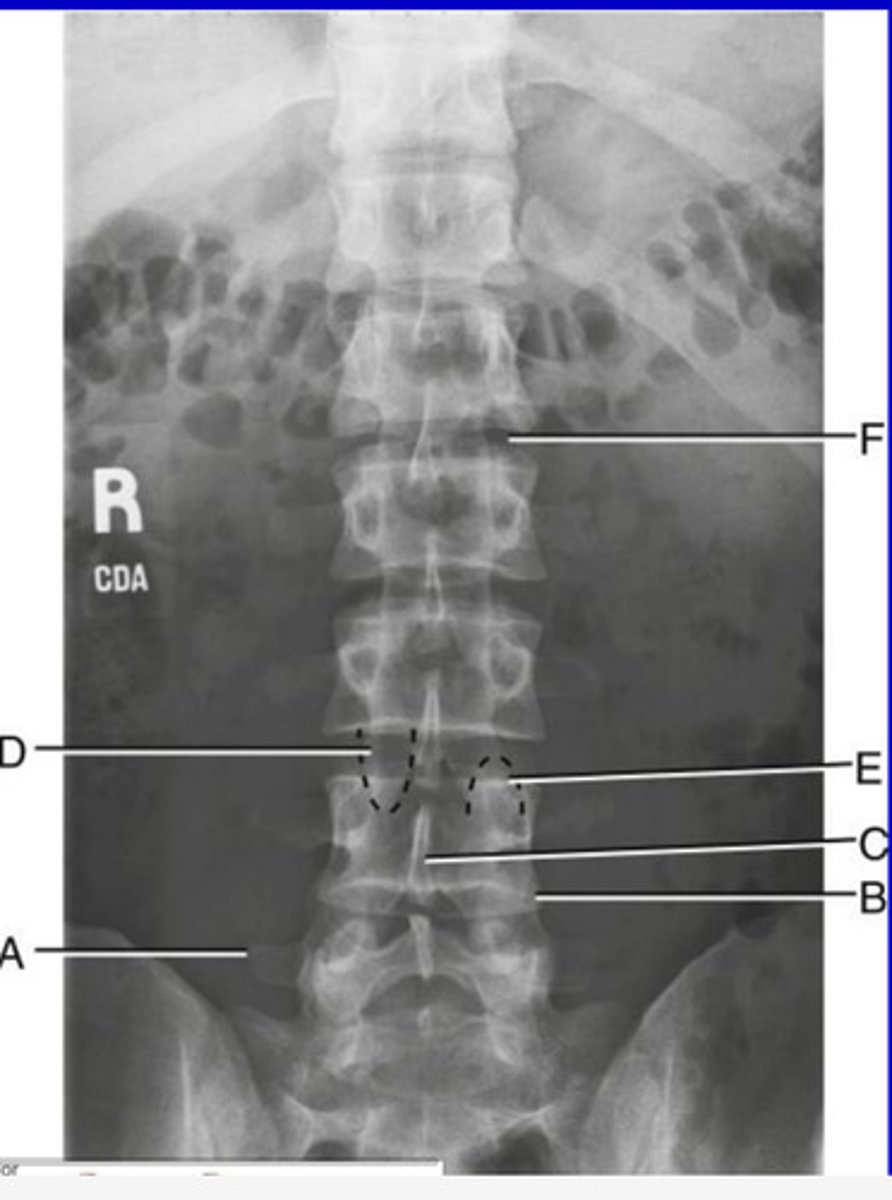

L5 R transverse process

A.

L4 Lower lateral portion

B.

L4 spinous process

C.

L3 R inferior articular process

D.

L4 L superior articular process

E.

L1-2 intervertebral disk space

F.

AP Lumbar

What position?